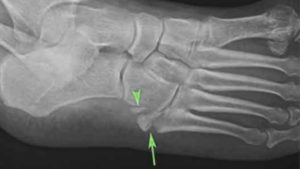

Рис — На рентгенограмме стопы — краевой перелом кубовидной кости и бугристости V плюсневой кости (показано стрелочками)

Чтобы убедиться в правильности постановки диагноза, травматолог после осмотра направляет пациента на рентгенологическое исследование. На снимке можно рассмотреть есть ли перелом, насколько ровные костные края, есть ли смещение отломков.